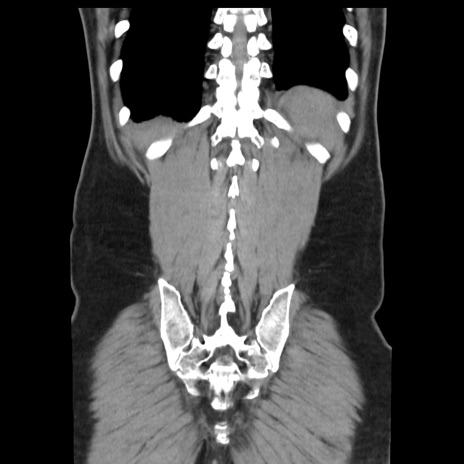

症例16(冠状断像)

【症例】 70歳代男性

【主訴】 腹痛、嘔吐

【現病歴】 約1ヶ月前より間欠的に腹痛と嘔吐あり、当院消化器内科を受診したところCTで多発する肝臓のLDAを指摘され、精査中であった。以降は消化器症状は安定していたが、2日前より嘔気と腹痛があり、同日より排便・排ガスが消失した。改善認めず、 本日、救急外来を受診した。

【既往歴】 大腸ポリープ切除後。

【身体所見】意識清明・会話良好、BT 36.3℃、BP 127/80mmHg、 P 80bpm、腹部:膨満あり、平坦・軟、上腹部正中および下腹部正中に圧痛あり、反跳痛なし、筋性防御なし。

【データ】WBC 7200、CRP 0.77